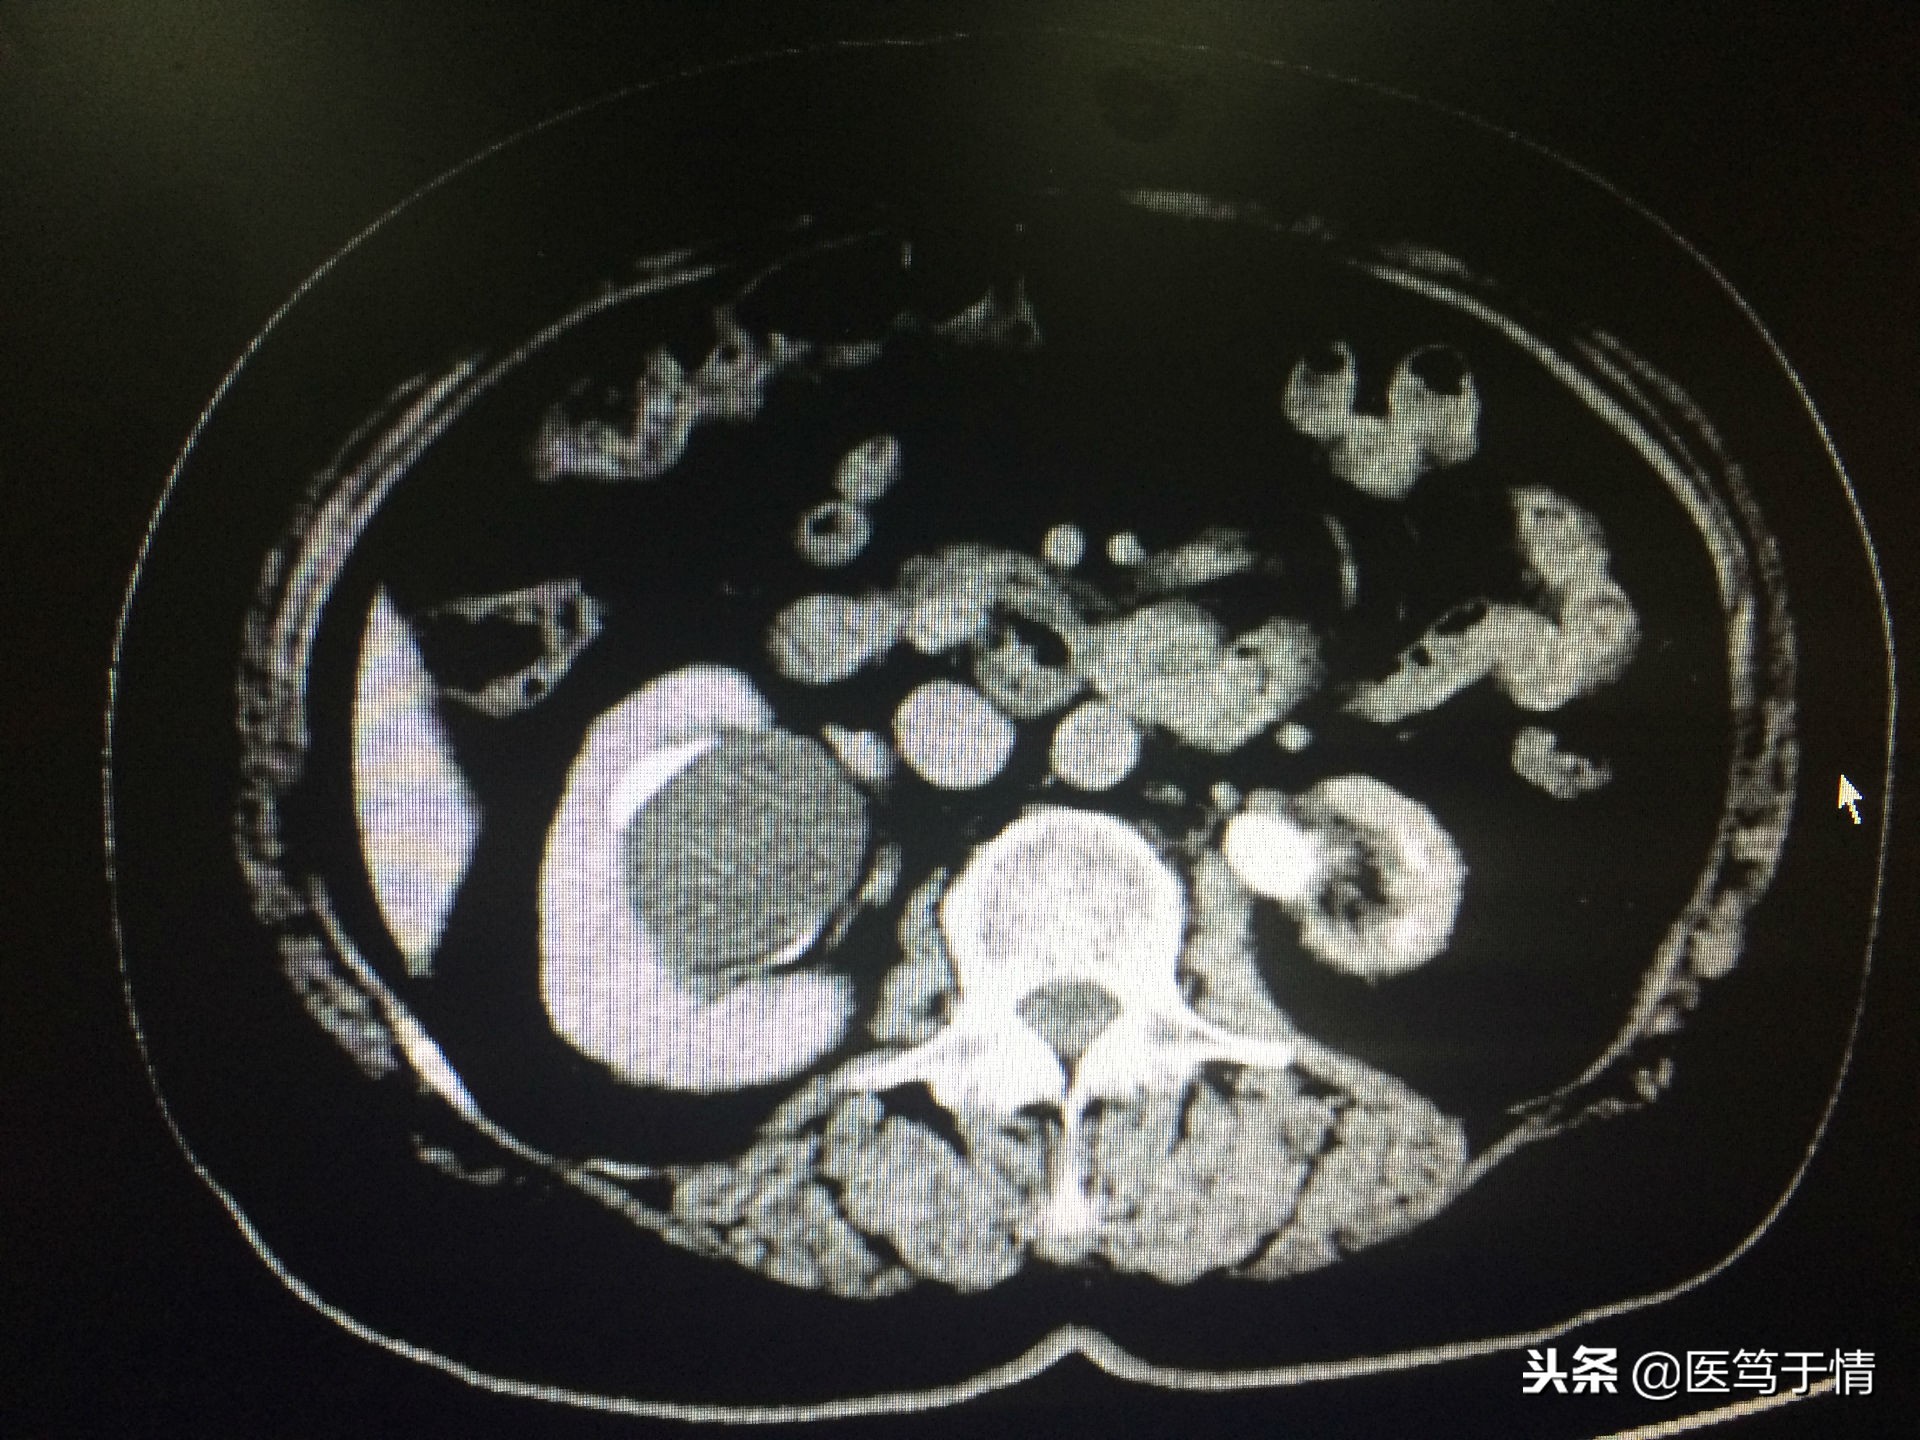

图三:女,67岁,右肾肾盂旁囊肿;